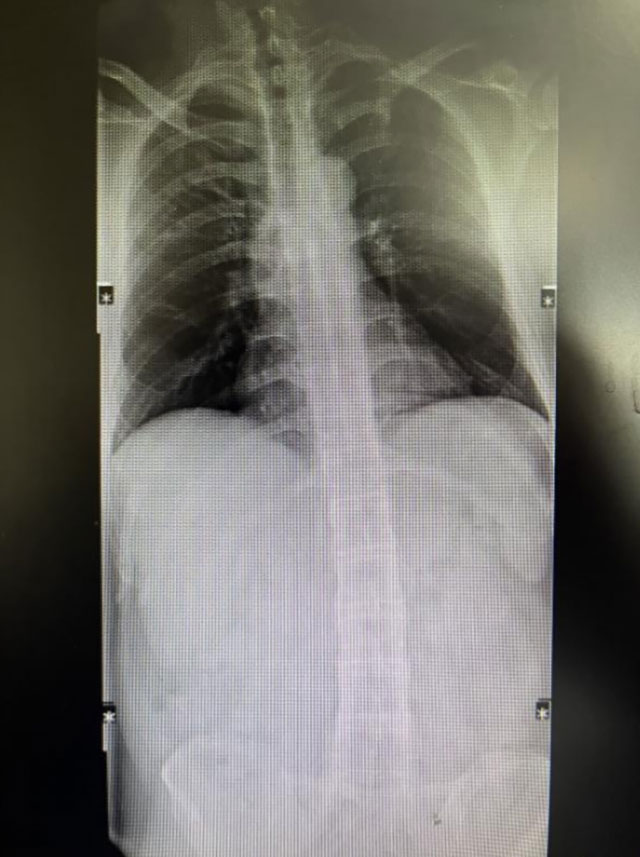

近几年,30岁的朱先生经常感觉腰背部疼痛,当地医院检查后诊断为“腰肌劳损”。为此,朱先生做过针灸理疗等对症保守治疗,也吃了中药,但症状反复,疗效欠佳。随即,朱先生来到了西南医科大学附属中医医院骨伤科脊柱·肿瘤二组就诊。黄天宇主治医师接诊后仔...